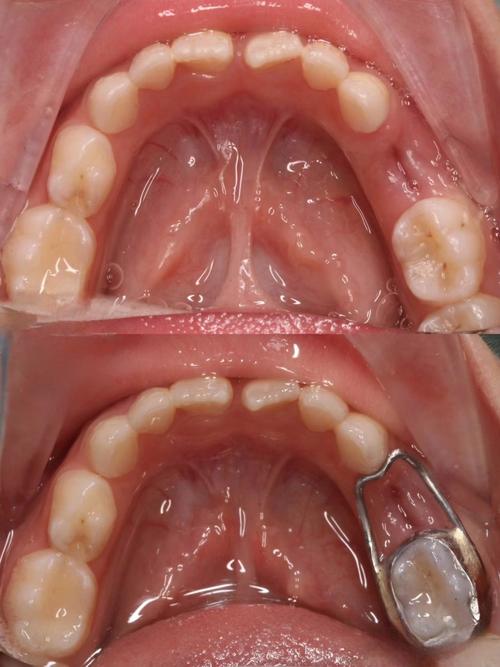

牙齿脱落的本质是支持组织(牙周膜、牙槽骨)的破坏或牙根本身的损伤,正畸治疗中需警惕以下三类核心风险:

牙齿移动依赖牙槽骨的生理性改建:受压侧牙槽骨吸收,牵引侧新骨形成,若施加力量过大、移动速度过快(如“快速矫正”技术滥用),或牙齿移动方向与牙根长轴角度偏差过大(如“倾斜移动”未控制转矩),可能导致牙根尖部持续受压,引发牙根吸收(尤其是颈1/3或根尖1/3的“特发性吸收”),严重时牙根变短、变细,牙齿固位力下降,咀嚼时易出现“浮动感”,最终脱落,多颗牙齿同时移动时,若支抗设计不当(如支抗牙受力不足导致移位),可能造成咬合力分布异常,加速个别牙松动。

- 牙根与骨量异常:锥形牙(牙根细小)、短根牙(如某些遗传性疾病)或牙槽骨薄(如上颌前牙区骨量不足),牙齿移动时易发生根穿或骨开裂;